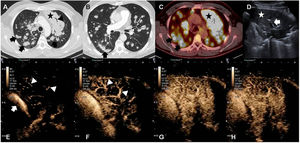

We report the case of a 58-year-old man with Langerhans cell histiocytosis with skin and lung involvement, diagnosed by biopsy. Lung biopsy was performed by thoracoscopy with atypical resection of the right lower lobe. After 3 years of follow-up, a chest X-ray revealed opacity in the left apex and multiple bilateral nodules. Computed tomography (CT) and fluorodeoxyglucose (FDG) positron emission tomography (PET-CT) were performed, showing extensive lung involvement (see Fig. 1) manifesting as diffuse consolidation in the left upper lobe (LUL) and multiple pulmonary nodules, primarily with peribronchovascular distribution. Ultrasound pre- and post-intravenous contrast administration was also performed to guide the biopsy needle and obtain tissue for histological study. Images showed nodules and subpleural consolidations, along with extensive opacity in the LUL with air bronchogram (see Fig. 1). After the administration of ultrasound contrast in the LUL, late uptake (by the bronchial arteries) and early elimination were observed, suggesting malignant involvement.1 Two percutaneous core needle biopsies of 2 different lesions were performed under ultrasound guidance. Pathology diagnosis of the biopsies revealed Langerhans cell sarcoma (LCS). After 3 treatment lines, the patient progressed and died 9 months after diagnosis.

(A) Chest CT scan in lung window. Extensive consolidation in the left upper lobe (star) and multiple bilateral pulmonary nodules (arrows). (B) Chest CT scan in lung window showing suture material from atypical resection for biopsy (arrow). (C) PET-CT: mediastinal window. Increased FDG uptake in left upper lobe (star) and in multiple pulmonary nodules (black arrows). (D) Ultrasound: consolidation in left upper lobe (star) and air bronchogram (arrow) are shown. (E–H) Contrast-enhanced ultrasound. (E, F) Contrast uptake in pulmonary artery (arrow) and its branches (arrowhead). No parenchymal uptake is observed. (F) Delayed uptake in pulmonary parenchyma, indicating irrigation of the mass from the bronchial arteries.